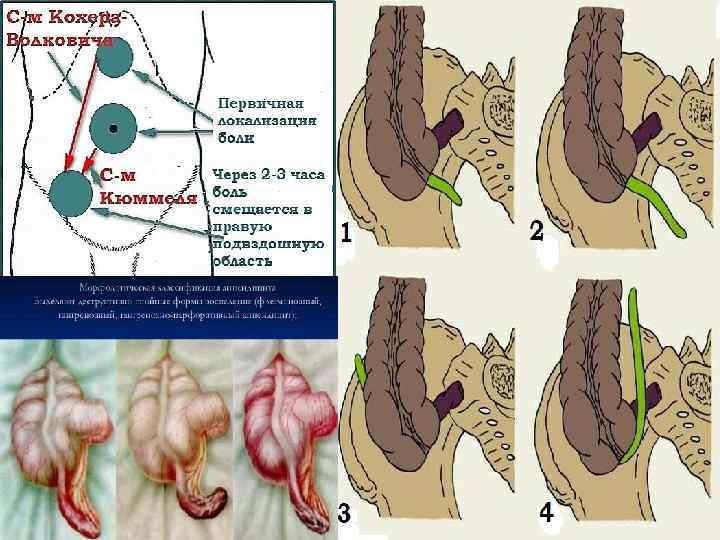

Острый аппендицит АНАМНЕЗ У 80% больных можно установить симптом Кохера Волковича: миграция ТУПОЙ боли из эпигастральной области в правую подвздошную в течение 2 3 часов. У 40% больных: одно двухкратная рвота приносящая облегчение(носит рефлекторный характер). Причем её наличие именно после появления клиники боли. У 25% больных: однократный жидкий стул. У 90% больных: субфебрильная температура 37 38*С

Клиническая картина Основные симптомы: Кохера Волковича – миграция боли из эпигастрия в правую подвздошную область. Раздольского – болезненность при перкуссии в правой подвздошной области. Воскресенского – скольжение правой рукой по натянутой рубашке от эпигастральной области к правой подвздошной с остановкой пальцев в проекции аппендикса. Ровзинга – прижатие в левой подвздошной области толстого кишечника вызывает усиление боли в правой подвздошной области. Образцова – усиление боли при поднятии выпрямленной в колене правой ноги. Ситковского – при перемещении больного на левой бок – усиление боли в правой подвздошной области. Бартомье Михельсона – болезненная пальпация в правой подвздошной области при положении на левом боку. Щеткина Блюмберга – сильная боль при пальпации в правой подвздошной области в момент резкого отнятия руки. Локальная/генерализованная ригидность мышц передней стенки брюшной полости. Симптом болезненности передней стенки прямой кишки – при «пальцевом» ректальном исследовании. Симптом нависания заднего свода влагалища – при влагалищном исследовании. Симптом «Токсических ножниц» учащенный пульс не соответствует температуре(при гангренозной форме).